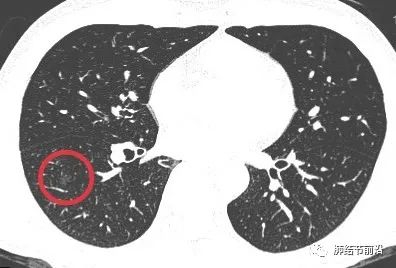

中年男性,不吸烟,2022.9月体检首次发现右下肺磨玻璃结节6mm,无前片对比。

患者口服头孢治疗2周,后三个月复查来诊。薄层CT显示,右下肺磨玻璃结节变成了相邻的数枚实性小结节。